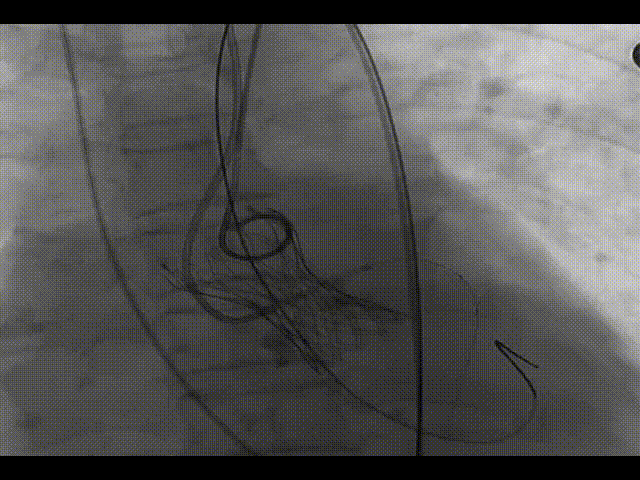

主动脉根部造影

左冠造影及保护

20mm球囊预扩,无漏,冠脉灌注良好

TaurusOne释放过程

食道超声辅助瓣膜定位

瓣膜完全释放

造影显示瓣膜形态欠佳

22mm球囊后扩

造影显示形态显著改善,微量瓣周漏